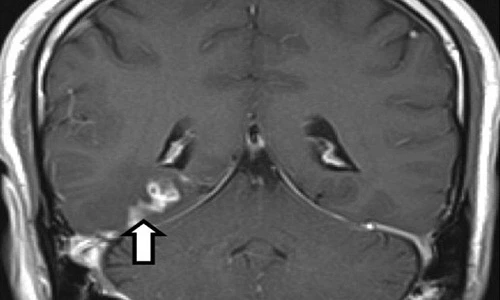

(Kiến Thức) - Dưới đây là những hình ảnh quét não của một con sán ký sinh trong não một người đàn ông ở Anh được các bác sĩ chụp lại.

Bác sĩ phẫu thuật tại Bệnh viện Addenbrooke ở Cambridge loại bỏ con sán dài 5cm trong não bệnh nhân suốt 4 năm trời.

Các bác sĩ khẳng định loài sán này mang tên Spirometra erinaceieuropaei, có nguồn gốc ở vùng Viễn Đông. Đây là trường hợp bệnh nhân cực kỳ hiếm, trên thế giới chỉ mới ghi nhận khoảng 300 trường hợp tương tự kể từ năm 1953.

Khi bị nhiễm loài sán này, nó có thể gây ra hội chứng Sparganosis, gây co giật, mất trí nhớ và đau đầu nghiêm trọng.

Các chuyên gia y tế cho rằng người bệnh có thể bị nhiễm loại sán này nếu ăn các loại giáp xác nhỏ, thịt sống có nhiễm loại sán này.

Tuy nhiên, thật may mắn cho bệnh nhân này là bác sĩ đã phẫu thuật loại bỏ thành công loài ký sinh trùng này, may thay đây chỉ là loại sán lành tính. Nếu nó thuộc loại ác tính, sán có thể hung hăng hơn bằng cách đẻ trứng, sau đó ăn hết não.